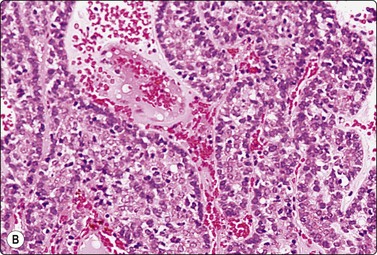

Kaposi’s sarcoma is mainly seen in the skin but also occurs in other sites in HIV-positive patients. The cytological findings are described in Chapter 5 and in Chapter 18, p. 459. The cytology of a few other types of cutaneous vascular tumors has also been reported.3,75,76 Ancillary techniques, especially immunocytochemistry may be necessary to establish a cytologic diagnosis of malignant vascular tumor of the skin, as such tumors display a wide spectrum of cytomorphologic patterns (Fig. 14.31).

image image

Fig. 14.31 Cutaneous angiosarcoma

Cutaneous angiosarcomas display a wide spectrum of cytomorphologic patterns. (A) FNB of epithelioid angiosarcoma (H&E, HP); (B) Positive staining with CD 31; liquid based preparation.